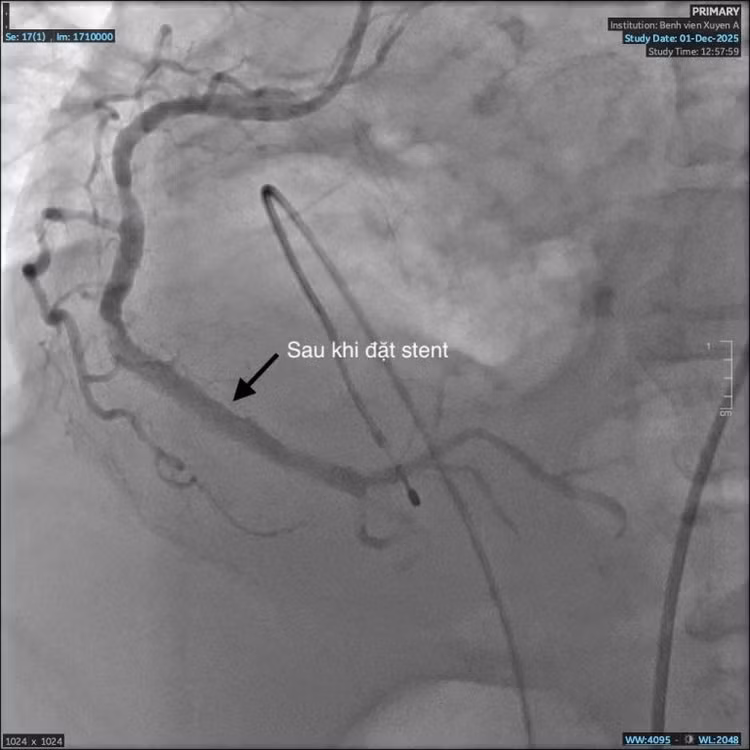

nhoi-mau-co-tim-3.jpg

Mạch máu sau khi đặt stent - Ảnh BVCC